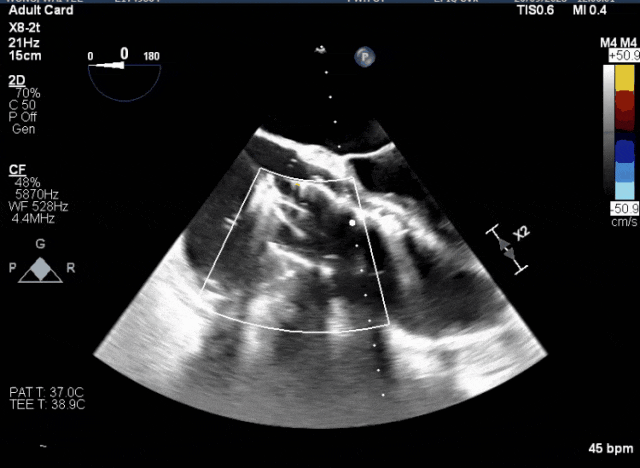

術前超聲顯示三尖瓣重度反流合并拴系

術中TEE成像困難,偽影干擾